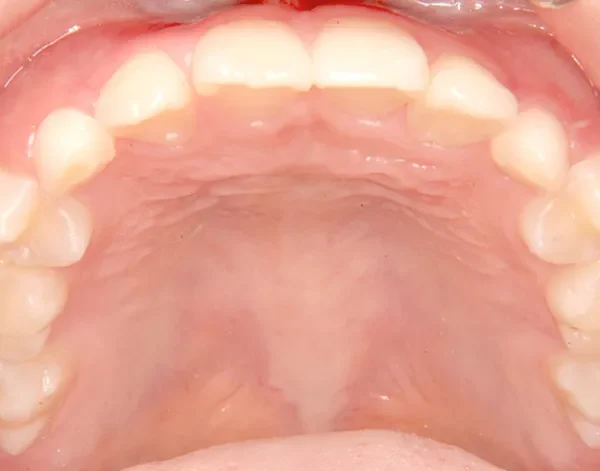

• 治療終了後

治療終了後

下の歯は永久歯の生えるスペースがないので、オリジナル矯正装置で受け口を治して、永久歯の生えるスペースを作りました。

治療回数19回、2年5ヶ月の治療期間で矯正治療を終了しました。

主訴が改善され、ご満足頂きました。